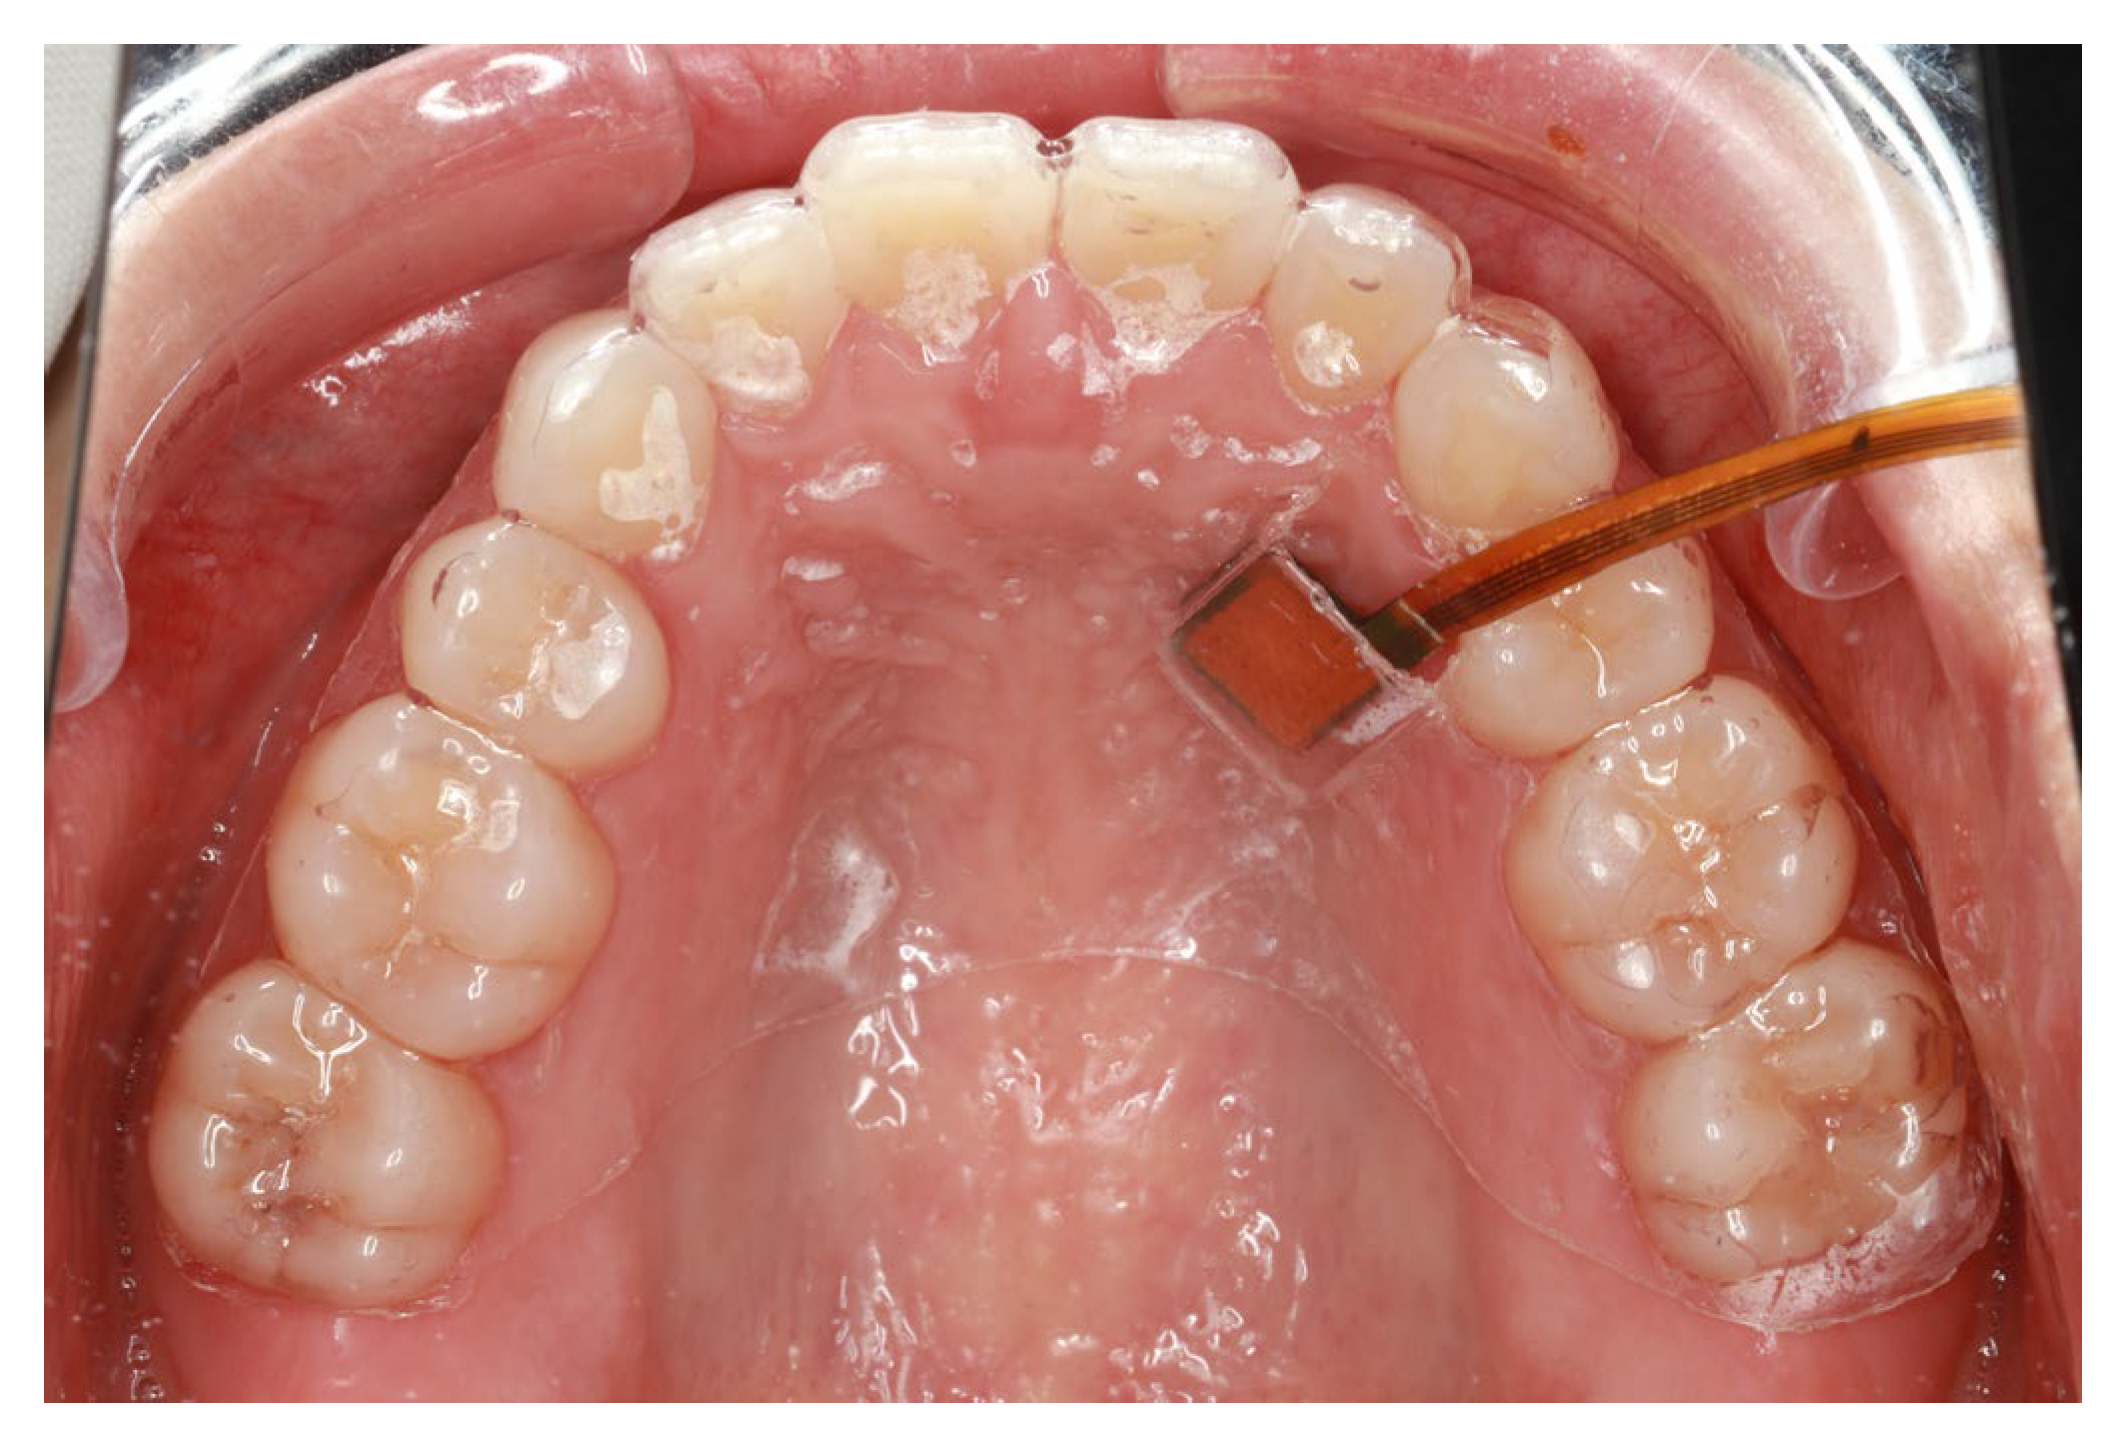

2.2.2. Method of Manufacturing the Mouthpiece Device

2.3.3. SpO2 and Pressure Measurements at Different Locations (Intraoral)

3.3.1. SpO2 and Pressure (Intraoral)